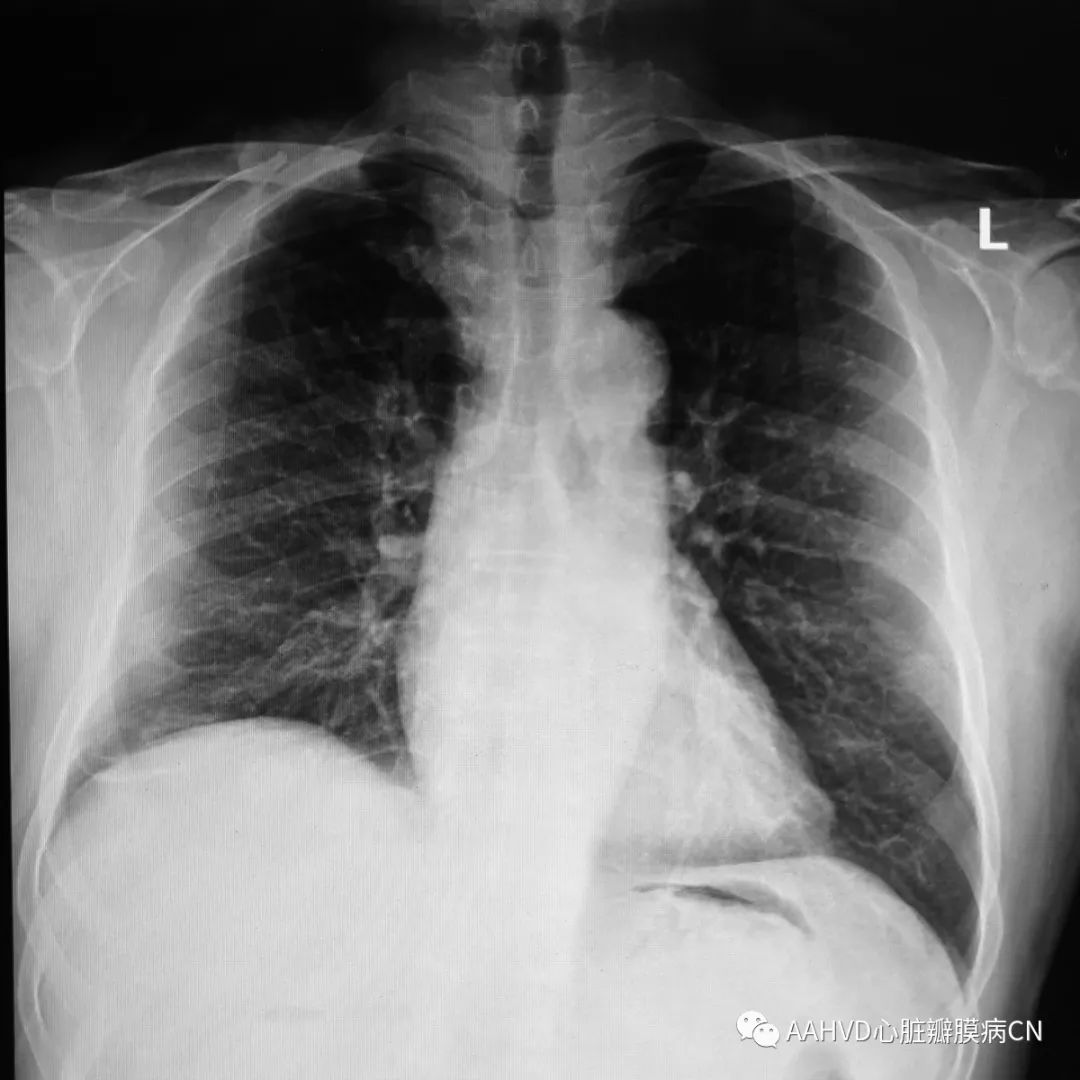

术前胸片

640_6